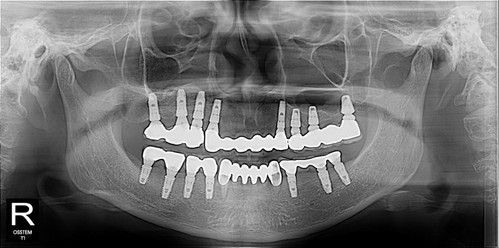

마지막 남은 두 개의 치아... 흔들리고 아팠지만 임플란트 수술이 너무 겁나서 참다가 참다가 딸이 데리고 오신 환자분

근데 다른 이는 다 임플란트라서 선택지가 없다.